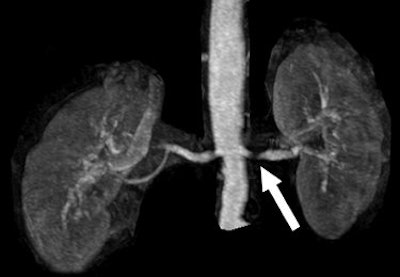

![]() |

| A 68-year-old man with severe stenosis of left renal artery. Anteroposterior maximum intensity projections of coronal 3D MR angiograms of abdominal aorta and renal arteries obtained with 0.2 mmol/kg of gadodiamide at 1.5 tesla (above) and 0.1 mmol/kg of gadodiamide at 3 tesla (below) show stenosis (arrow) equally well. |

| Herborn CJ, Runge VM, Watkins DM, Gendron JM, Naul JG, "MR Angiography of the Renal Arteries: Intraindividual Comparison of Double-Dose Contrast Enhancement at 1.5 T with Standard Dose at 3 T" (AJR 2008; 190:173-177). |